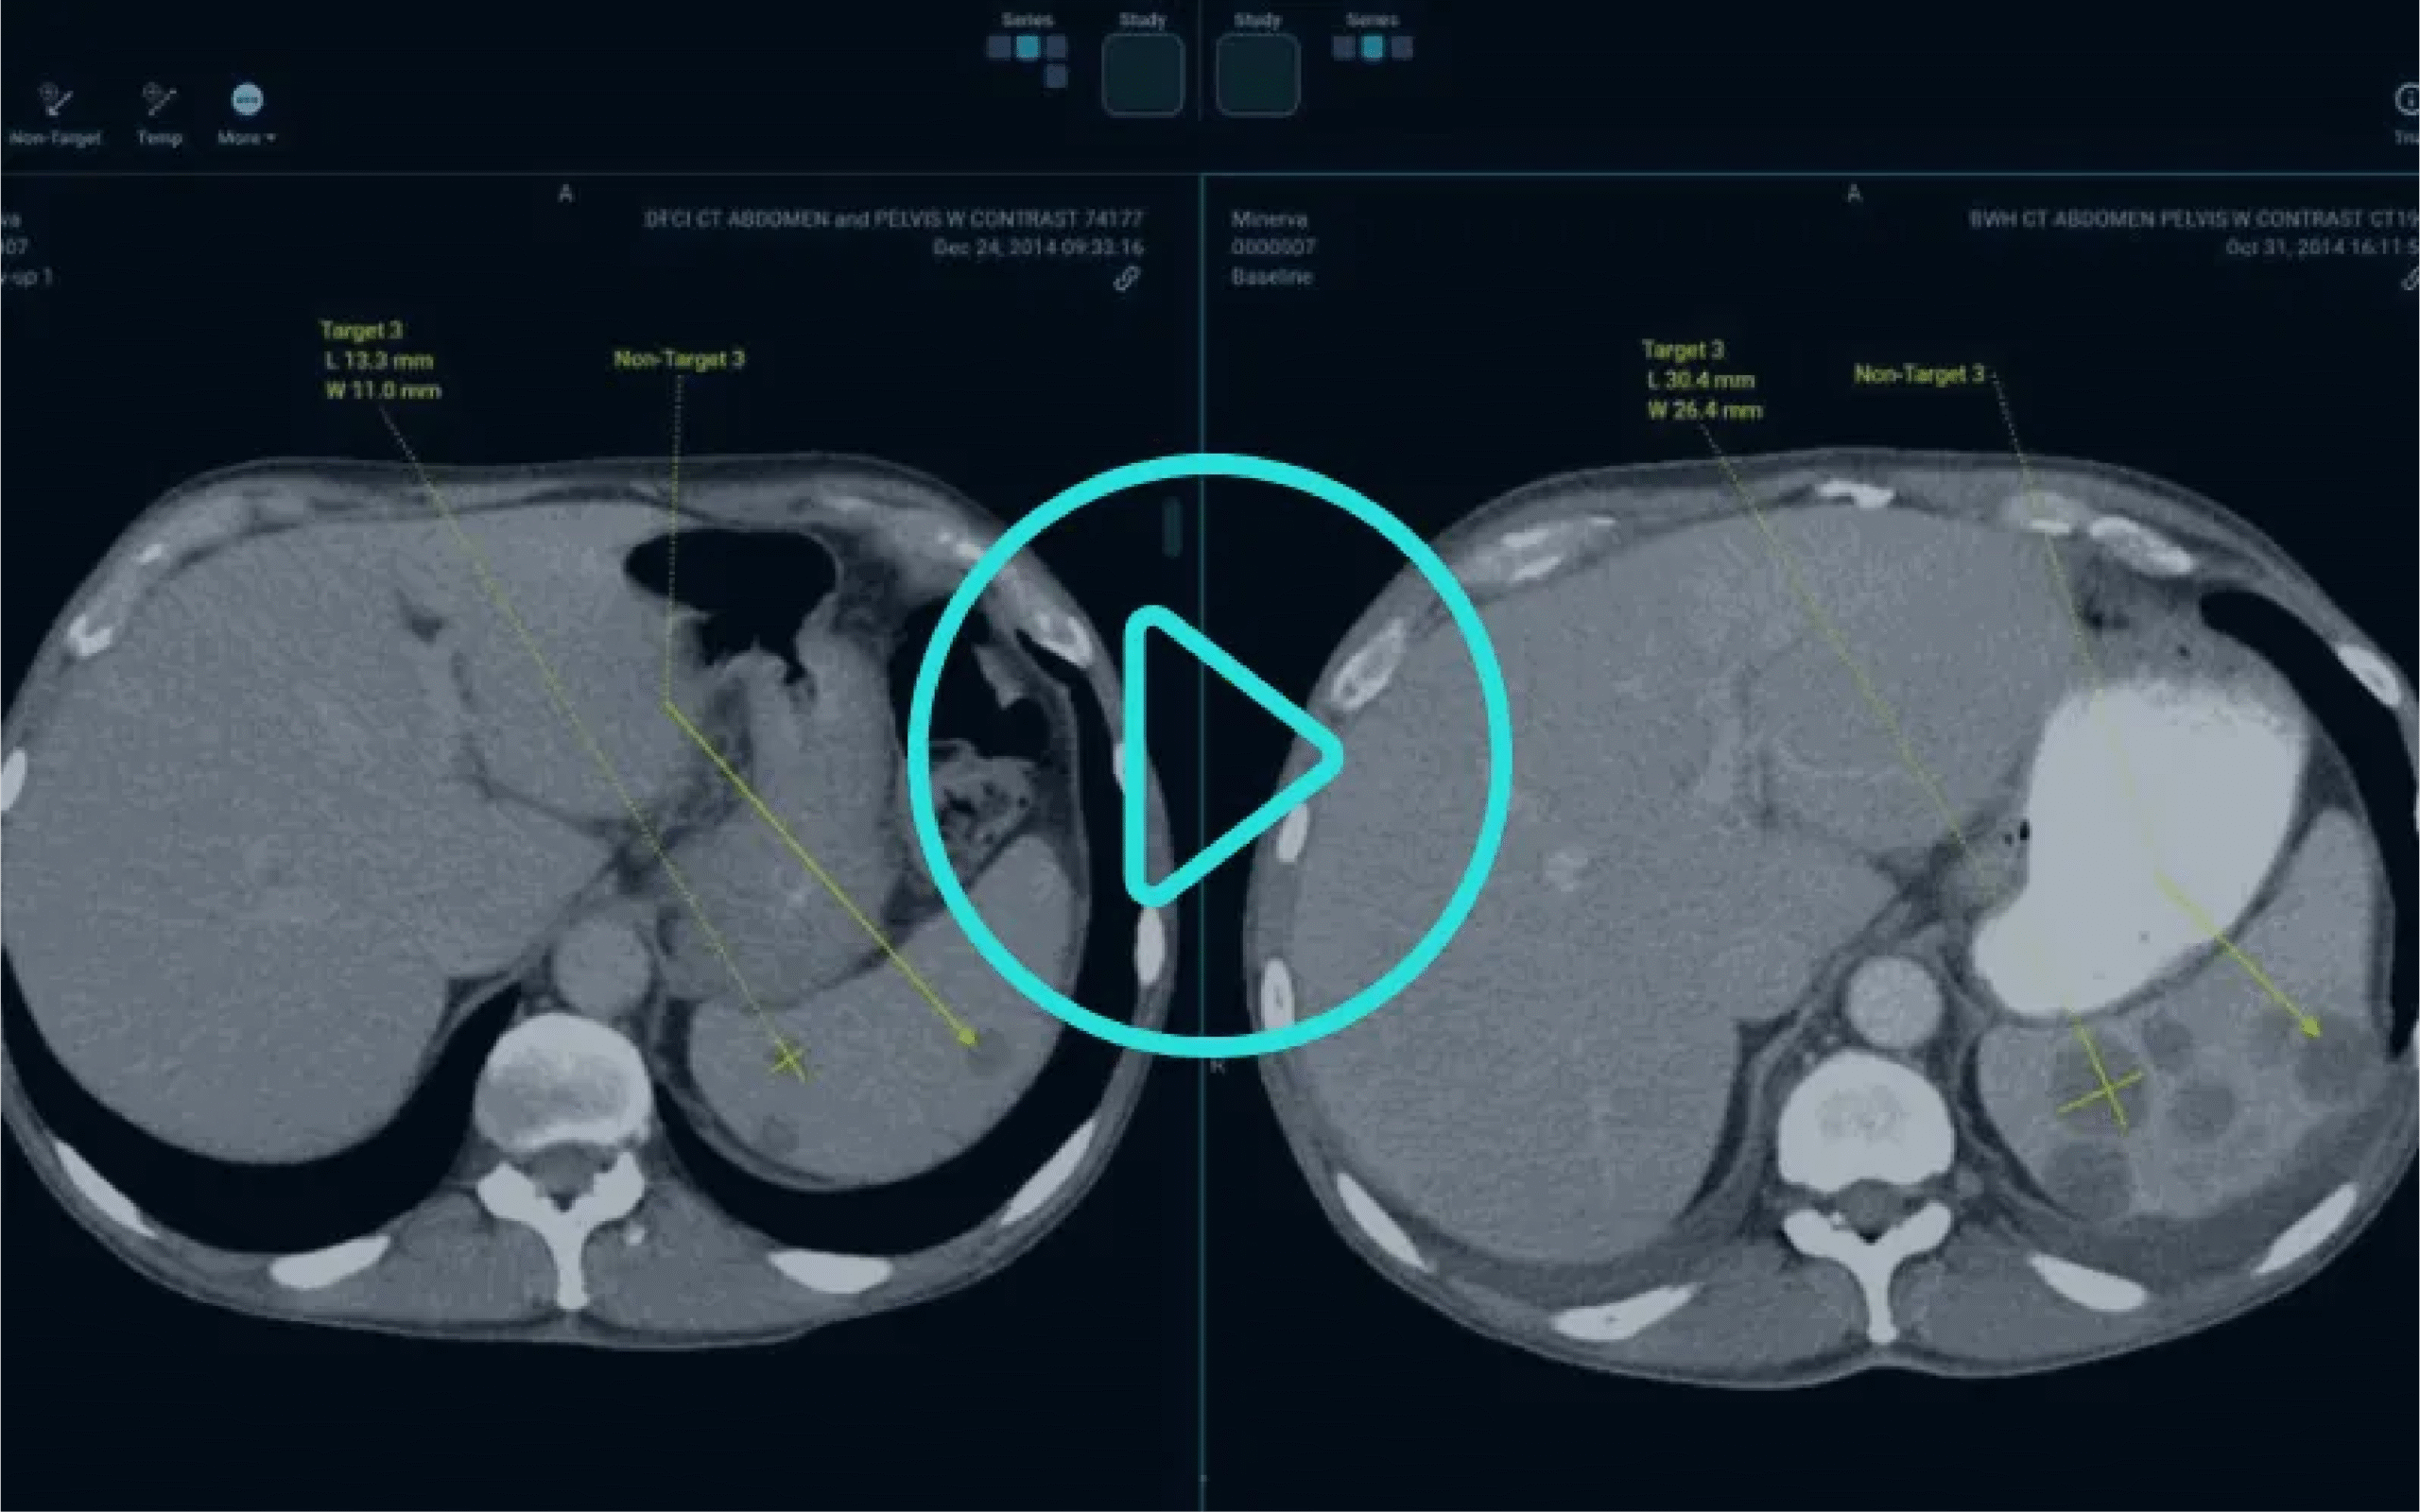

OHIF Viewer measuring tumor size to track oncology treatment progress over time

LesionTracker

LesionTracker is an image viewer based on the OHIF framework, tailored specifically for an oncology metrics workflow that is useful in clinical trials. It has specialized tools, UI elements, and logic for measuring tumors and following their progress (growth or shrinkage) over time, typically in response to a treatment as part of a clinical trial. This project is funded by the National Cancer Institute under a 5-year ITCR U24 grant.